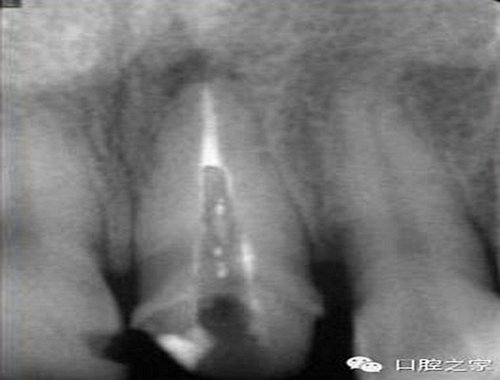

1.沖洗預(yù)備根管

大多數(shù)醫(yī)生在樁道預(yù)備時習(xí)慣于干燥預(yù)備根管(圖 1),這樣很容易破壞根管壁的牙本質(zhì)結(jié)構(gòu),同時也可形成較厚的玷污層,影響樹脂水門汀與牙體組織的粘接。因此,臨床操作時應(yīng)選擇沖洗的方法冷卻預(yù)備根管(圖 2),防止牙膠及封閉劑粘連附著于根管壁形成第二玷污層(根管治療時形成的玷污層稱為第一玷污層),有利于樹脂水門汀與根管牙本質(zhì)的粘接。

圖1:干燥預(yù)備根管。

圖2:沖洗預(yù)備根管。